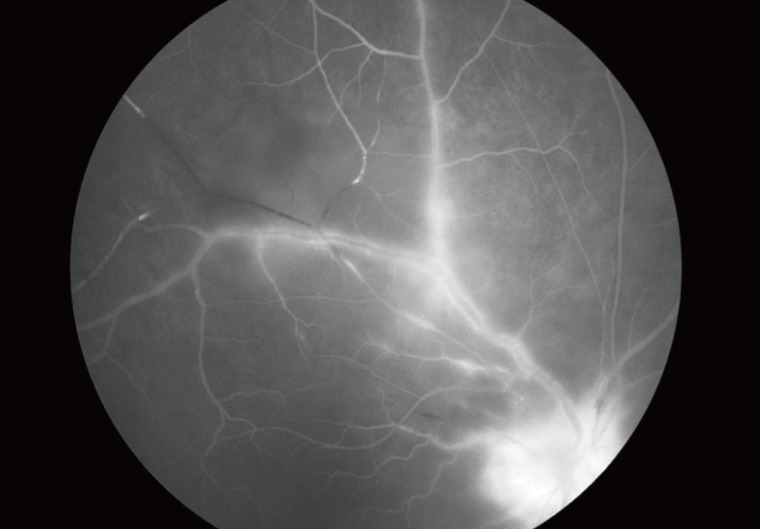

Fig. 3

Fluorescent angiogram of papillitis and vasculitis in an ocular toxoplasmosis patient.

kjp-51-393-g003.jpg

In typical cases, active lesions are seen as whitish foci of retinochoroiditis, frequently adjacent to a pigmented and/or atrophic scar (Fig. 2A-C). An active retinochoroidal lesion usually results in an atrophic retinochoroidal scar, which resolves from the periphery to the center of the lesion (Fig. 2D). Minority of patients with ocular toxoplasmosis may develop fociof inflammation within or directly adjacent to the optic nerve head. Whitish inflammatory lesions located on the disc with associated vitritis suggest the diagnosis (Fig. 3).